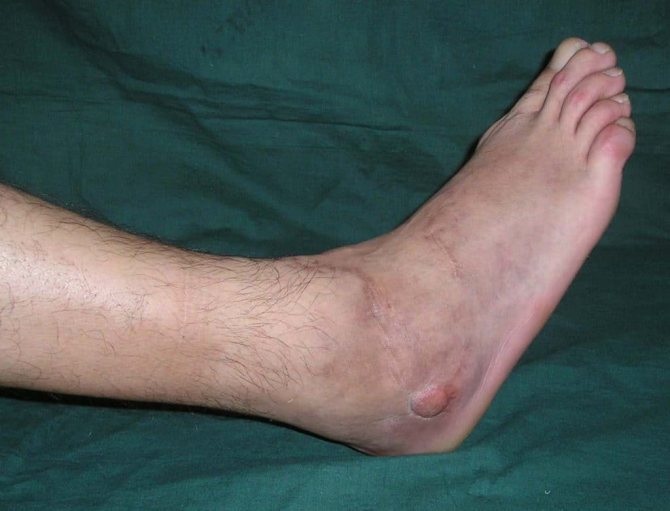

Отек и кровоподтек (синяк, гематома) – обе этих черты характерны для ушиба и перелома, однако скорость нарастания и выраженность данных симптомов могут быть разными. При ушибе отек менее выражен и нарастает медленнее. Если же случилось нарушение целостности кости, зачастую ткани отекают достаточно быстро. Кровоподтек при переломе может развиваться в течение нескольких дней, а при ушибе синяка может не быть вовсе.

К симптомам, определяющим перелом пальца, относятся те же, как и при переломах других локализаций. Чтобы точнее определить наличие такой травмы, симптомы подразделяют на две категории – достоверные и вероятные. К вероятным относятся: болезненность в месте перелома; наличия покраснения на возможном месте перелома; отечность мягких тканей; неестественное положение пальца; возникновение острой боли в месте перелома; повышение температуры тканей в месте перелома; невозможность произвольно двигать пальцем. Убедиться в правильности диагноза поможет рентген стопы.

К достоверным признакам перелома относятся: наблюдается костный дефект при ощупывании кости; патологическая подвижность кости; заметная деформация кости; может наблюдаться укорачивание сломанного пальца; крепитация костных отломков.